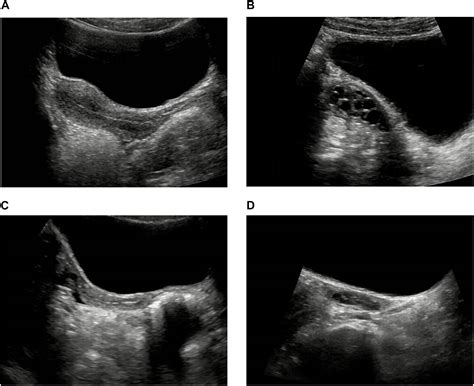

A sonographic examination of the ovaries is a safe procedure that uses high-frequency sound waves to create images of the pelvic organs. In the context of a Normal Ovary Sonography, a radiologist or sonographer looks for specific markers that indicate the organ is functioning within standard medical parameters. Typically, the ovaries appear as almond-shaped structures located on either side of the uterus. They are characterized by their hypoechoic (darker) stroma and the presence of small, fluid-filled sacs known as follicles.

The appearance of the ovary can shift significantly depending on the patient’s age and the current phase of the menstrual cycle. For example, during the follicular phase, it is common to see several small follicles growing, which is a perfectly healthy sign of reproductive activity. Recognizing these variations is the key to identifying what constitutes a normal ultrasound versus one that requires clinical intervention.

• Follicular Pattern: The presence of multiple, small (typically under 10mm) anechoic structures arranged peripherally or scattered is a hallmark of healthy, active ovaries.